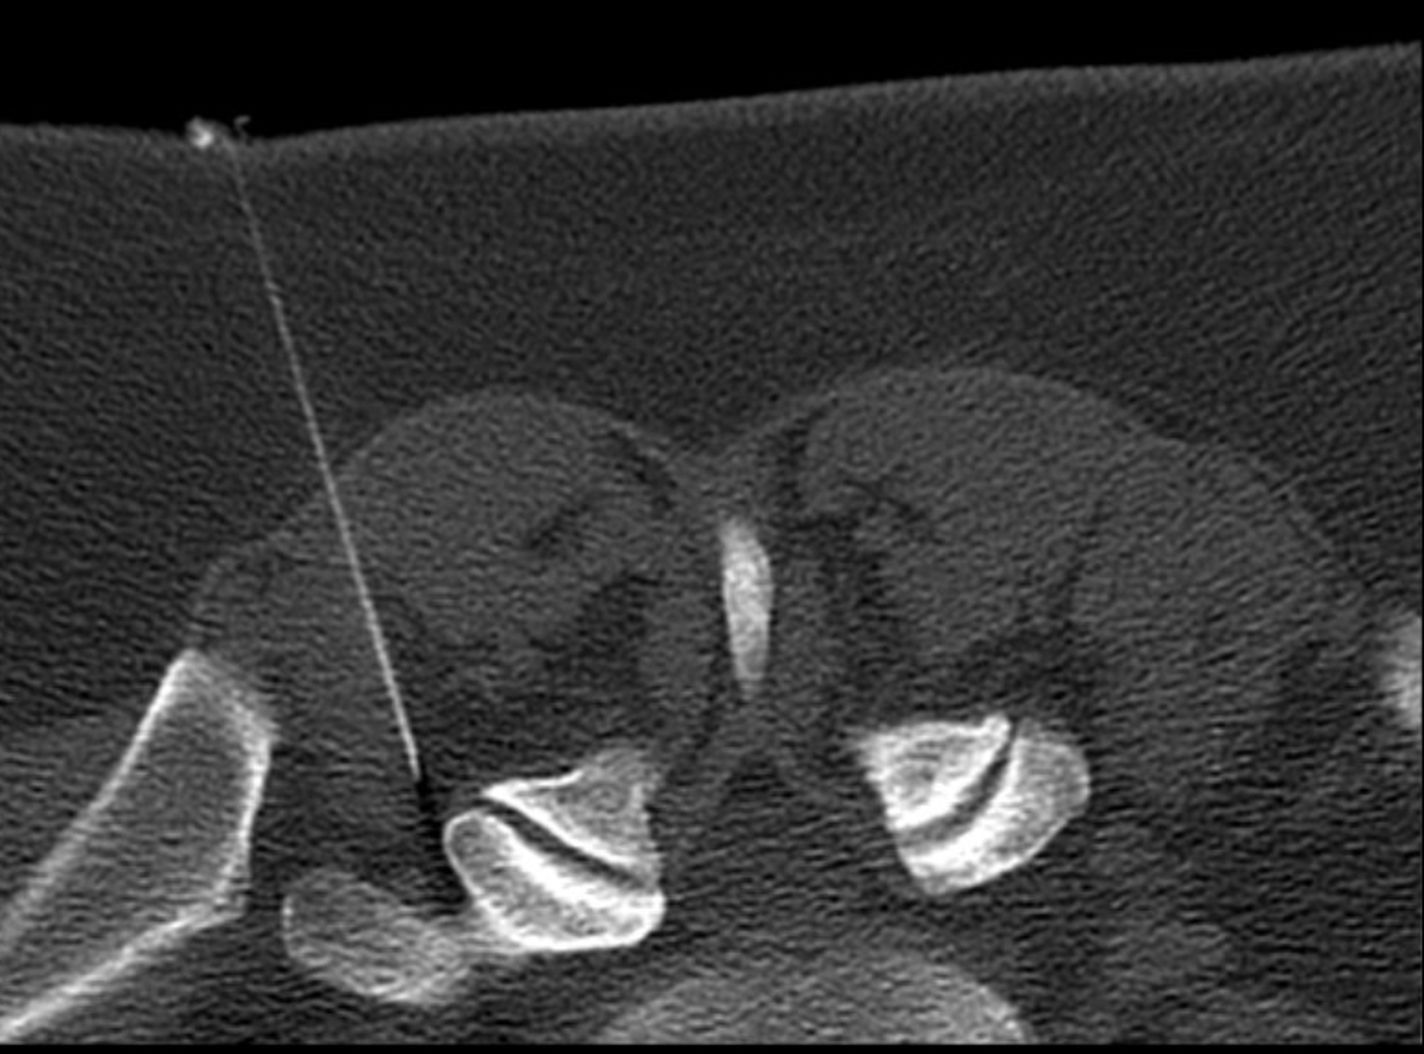

Die PRT ist eine Behandlung chronischer Schmerzzustände bei degenerativen Wirbelsäulenerkrankungen, insbesondere im Bereich der Hals- und Lendenwirbelsäule. Bei der PRT wird eine dünne Injektionsnadel unter computertomografischer Kontrolle nahe an eine Nervenwurzel im Bereich der Wirbelsäule geführt. Dort kann man gezielt und sehr genau lokal Medikamente einbringen, um chronische Schmerzzustände zu lindern.

Die Behandlung erfolgt im Computertomographen, wo gezielte Aufnahmen der Region zur Lokalisation der zu behandelnden Stelle, zur Lagekontrolle der Nadel ggf. auch mit Gabe einer geringen Menge von Kontrastmittel angefertigt werden (siehe auch Computertomographie).

Vor Durchführung der PRT muss zuverlässig der betroffene Wirbelkörper und seine Nervenwurzel identifiziert werden. Hierzu wird vor Durchführung der Therapie am besten eine Kernspintomographie oder auch eine Computertomographie angefertigt. Das Bekannte zu behandelnde Wirbelkörpersegment wird unter Kontrolle mit einem Computertomographen (CT) eingestellt und abgebildet (Einstellungsmessung). Hierdurch kann Stichrichtung und Stichtiefe gesteuert werden. Die Injektionsnadel wird dann mithilfe eines Ziellasers möglichst nah an die Nervenwurzel platziert und ein antientzündliches Medikament (in der Regel ein Lokalanästhetikum und Kortison) gespritzt. Der Therapieeffekt beruht darauf, ein entzündungshemmendes Medikament möglichst nahe an die schmerzhaft gereizte und geschwollene Nervenwurzel heranzubringen. Das Ziel ist, hierdurch den der Teufelskreis aus Druck, Nervenschwellung und dadurch noch mehr Druck zu durchbrechen (abschwellender Effekt).

Die Patienten werden zunächst auf dem Bauch gelagert, die zu behandelnde Stelle wird sorgfältig desinfiziert. Dann wird (ggf. mit lokaler Betäubung) unter Bildkontrolle eine dünne Nadel vorsichtig an die Wirbelsäule herangeführt. Die korrekte Lage der Nadelspitze wird, falls erforderlich, mit einem Kontrastmittel überprüft. Bei guter Nadellage wird anschließend eine Mischung aus einem stark wirkenden entzündungshemmenden Medikament (im Regelfall Cortison) und einem lokalen Betäubungsmittel gespritzt. Die Behandlung dauert ca. 5 – 10 Minuten. Eine Besserung tritt meist nach wenigen Tagen auf. Wir führen in der Regel 3 Behandlungen, jeweils im Abstand von einer Woche durch. So erreichen wir häufig auch länger anhaltende Besserung der Beschwerden.